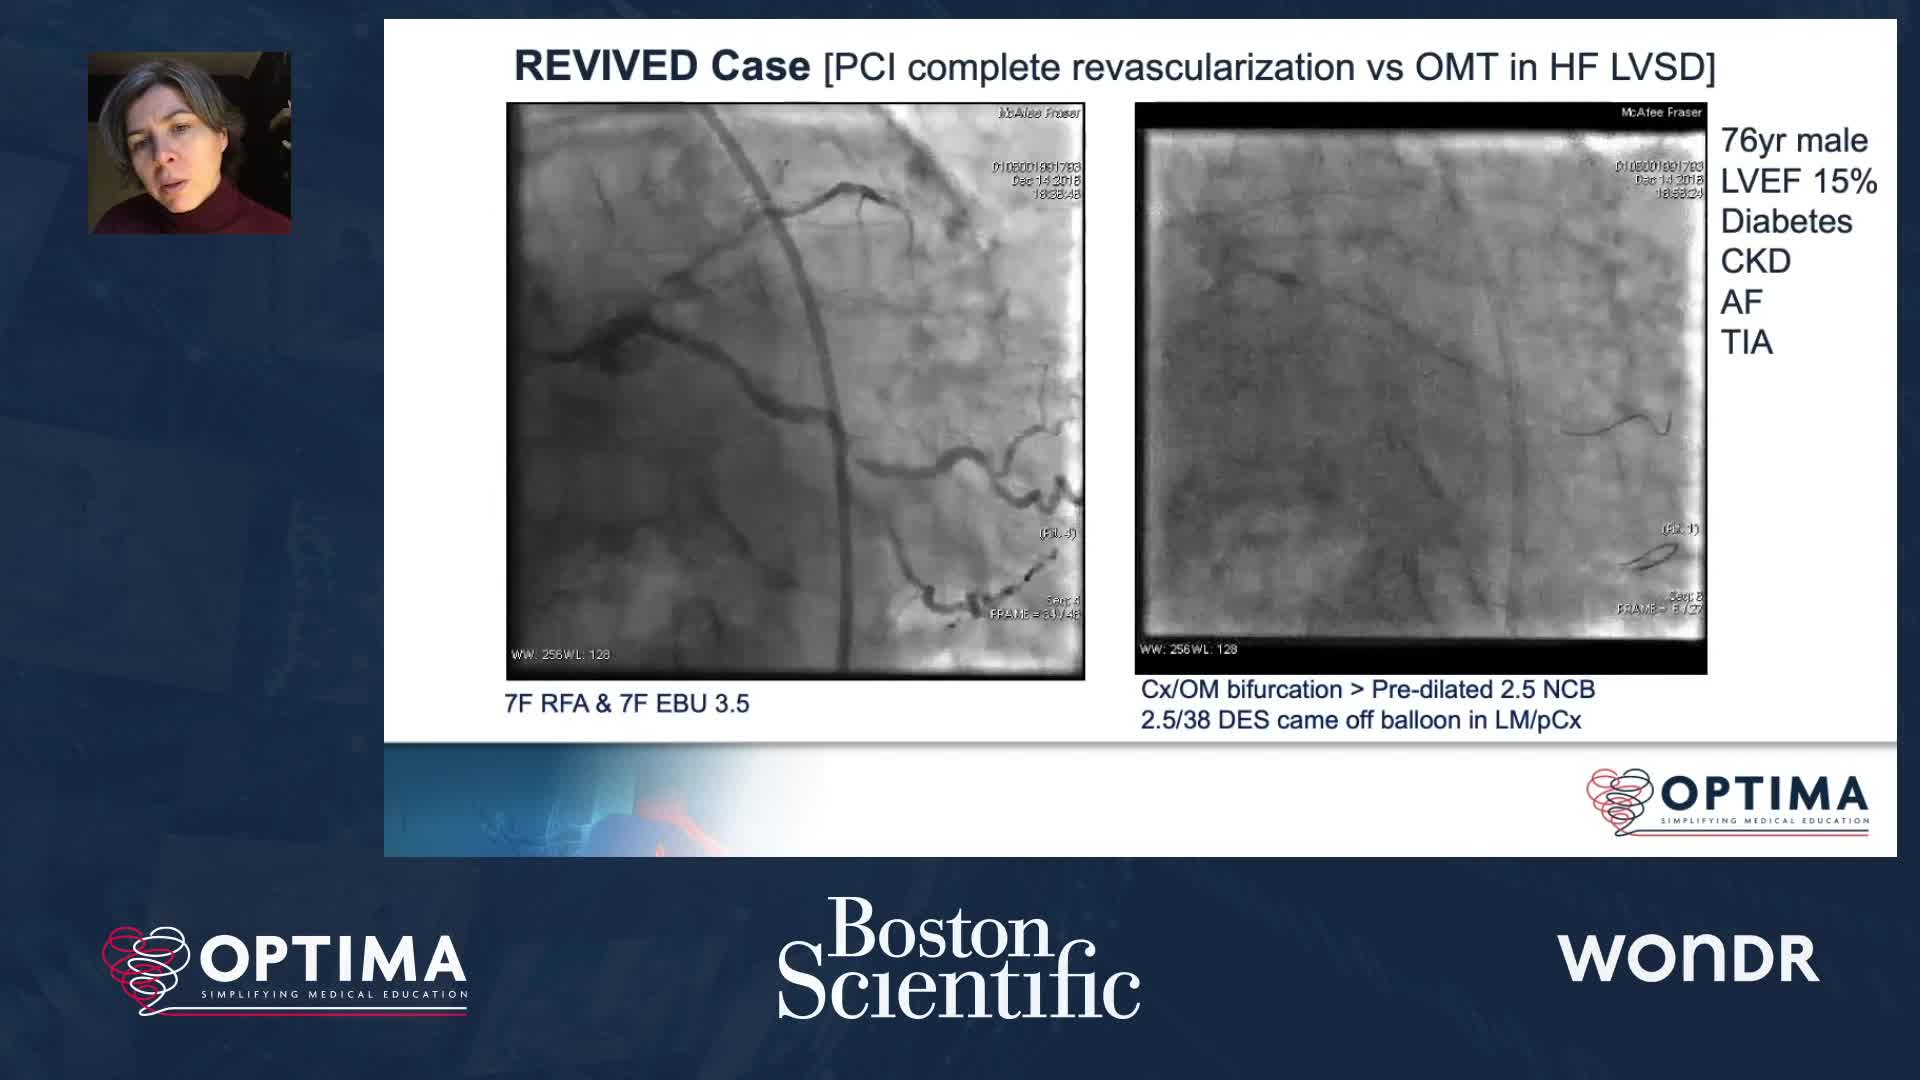

Session 4: High-risk and complex – too tough to treat?

Optimal Online 2020 - Day Four Highlights